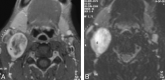

Results: The schwannomas were solitary, well-circumscribed, and medial to the carotid sheath. Seven were hypoattenuated to skeletal muscle on CT with poor postcontrast enhancement, 4 were isoattenuated, and a single lesion showed intense heterogeneous enhancement. At MR imaging, they were heterogeneously bright on T2WI with intense inhomogeneous postgadolinium enhancement. The ICA was displaced anteriorly in 9 patients with a component of lateral displacement in 8 of these patients. The ICA was in a neutral position in 2 patients and posterolaterally displaced in 1 patient. A single patient demonstrated separation of the ICA and IJV. There was splaying of the carotid bifurcation in 4 patients.